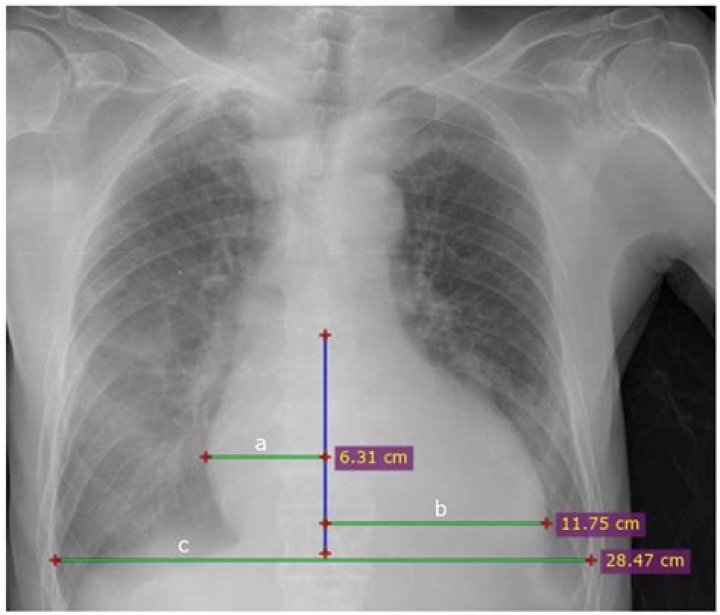

How to diagnose cardiomegaly on chest x ray?

Transverse cardiac diameters of 15.5cm for males and 14.5cm for females are considered as the normal upper limits respectively; An increase in the transverse cardiac diameter by 1.5cm on two consecutive chest radiographs taken at short intervals is considered abnormal, and a sign of cardiomegaly.

Chest x-ray -Cardiothoracic Ratio -CARDIAC SIZE - Cardiomegaly